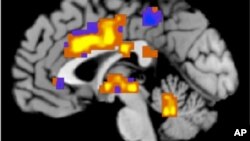

นักวิทยาศาสตร์จัดทำแผนที่สมองหนูที่ละเอียดมากที่สุดออกมาสองแผนที่เพื่อใช้เป็นเครื่องมือสำหรับนักวิจัยในการสร้างความเข้าใจถึงการทำงานของสมองตลอดจนเพื่อศึกษาโรคในสมองรวมทั้งโรคอัลไซม์เมอร์สกับโรคออติสซึ่ม

ผู้เชี่ยวชาญชี้ว่าสมองของหนูมีความคล้ายคลึงอย่างมากกับสมองของคนแต่สมองของหนูมีเซลล์ประสาทนิวรอนราว 100 ล้านเซลล์และมีความซับซ้อนน้อยกว่าสมองของมนุษย์ ทำให้ง่ายในการศึกษามากกว่าสมองคน

ทีมนักวิทยาศาสตร์ที่ร่างแผนที่สมองของหนูเป็นนักวิจัยแห่งสถาบัน Allen Institute for Brian Science พวกเขาทำการตกแต่งพันธุกรรมเชื้อไวรัสไข้หวัดชนิดหนึ่งให้อ่อนแอลงและให้ผลิตโปรตีนเรืองแสงได้

หัวหน้าทีมนักวิจัยกล่าวกับผู้สื่อข่าววีโอเอว่าเชื้อไวรัสไข้หวัดทำให้เซลล์ประสาทในสมองบางส่วนติดเชื้อและเซลล์ประสาทที่ติดเชื้อไวรัสแต่ละเซลล์จะเรืองแสงได้ทำให้นักวิจัยมองเห็นเครือข่ายการโยงใยของเซลล์ประสาทได้ตลอดความยาวของเส้นประสาท

หลังจากนั้น ทีมนักวิจัยใช้หุ่นยนต์ในการผ่าสมองของหนูทดลองออกเป็นชิ้นบางเฉียบ แล้วถ่ายภาพผ่านกล้องจุลทัศน์ที่เเสดงให้เห็นเครือข่ายของเส้นประสาทนิวรอนที่เรืองเเสง